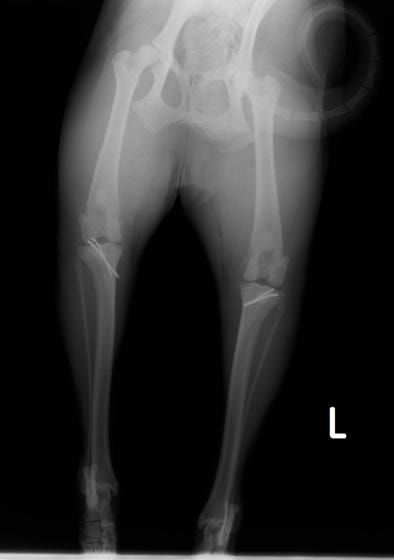

■ 症例22 ポメラニアン 1歳5か月 去勢雄

左後肢の挙上を主訴に来院した。整形学的検査、レントゲン検査より左右の膝蓋骨脱臼(左GradeⅡ〜Ⅲ、右Grade Ⅱ)を認めた。また、脛骨の前方引き出し試験の際に、引き出し兆候は認められないものの、疼痛が認められたため、前十字靭帯の損傷が疑われた。術中における、目視および関節内の操作によって、前十字靭帯の損傷や過伸展といった異常が認められなかったため、膝蓋骨脱臼の整復のみ実施した。手術手技は縫工筋及び内側広筋の解放、脛骨粗面の外側転位、滑車ブロック形造溝術、内外側関節包の縫縮を実施した。本症例は跛行もなく経過良好である。しかし、頸骨高平部の角度(TPA)が 右26.2°、左24.9°であり、解剖学的に前十字靭帯損傷のリスクが高いことから今後の経過に注意が必要である。